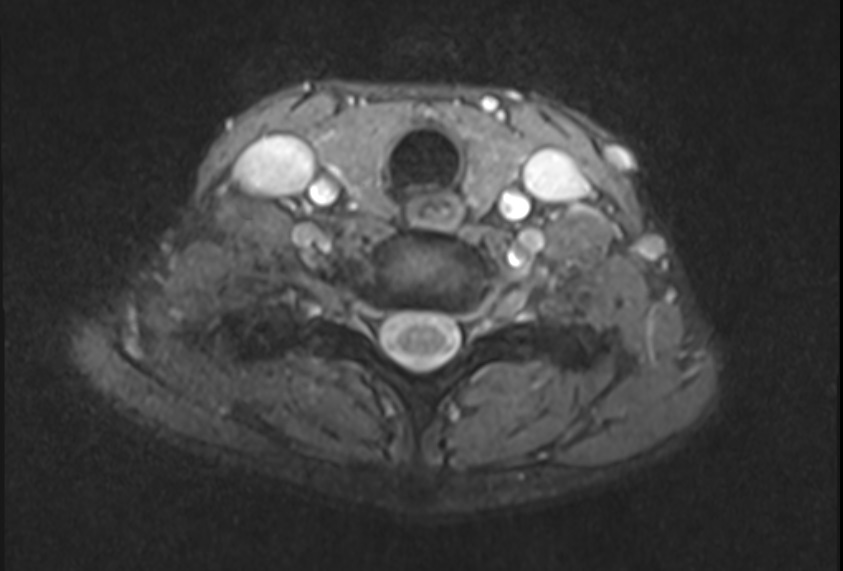

Анатомия внутренней яремной вены: КТ изображения